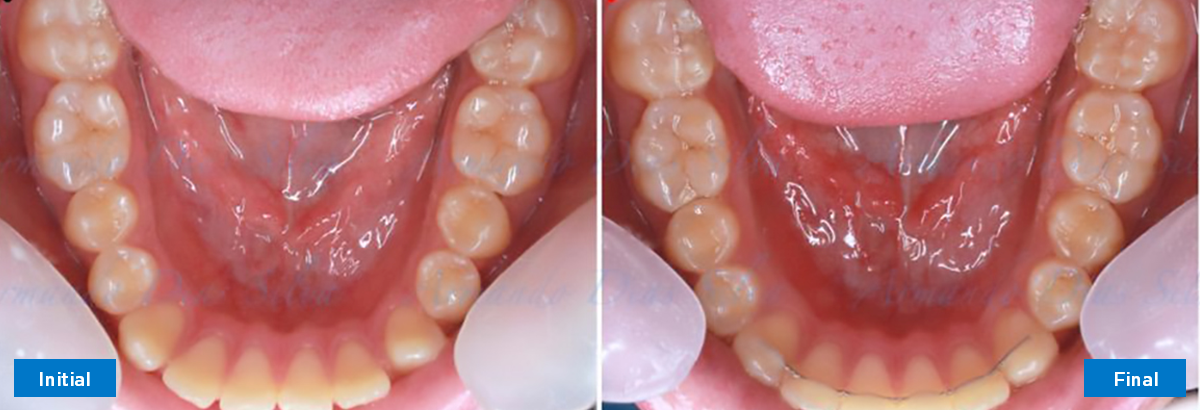

• Espaciamiento leve de las arcadas superior e inferior (deficiencia transversal de 3,45 mm)

• Deficiencia transversal maxilar leve (3,45 mm)

• Alinear y nivelar sin extracciones

• Desrotar y distalizar los molares superiores

• Retruir los incisivos superiores

Duración: 7 meses, 7 citas

N.º de alineadores -Superior: 24 Inferior: 16